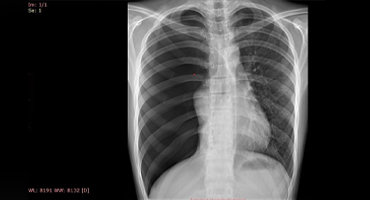

ARCO COSTAL BIFIDO

Rayos X